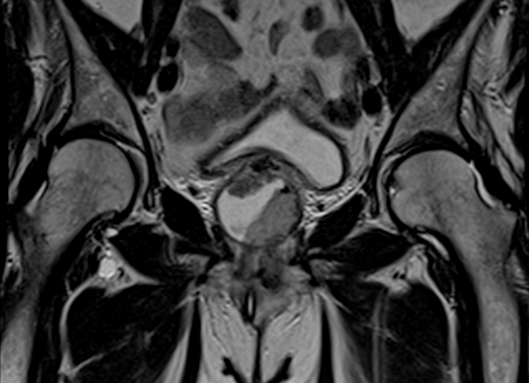

Paciente femenino de 64 años, sin antecedente de tabaquismo o historia de infeciones de vías urinarias, quien acude a consulta por presentar síntomas urinarios como disuria, urgencia y frecuencia urinaria de un mes de evolución, además de presentar ocasionalmente hematuria macroscópica sin coágulos. En la exploración física se encontró en el tacto vaginal un aumento de volumen en la pared anterior vaginal, no dolorosa, dependiente de la uretra proximal. En el examen general de orina se encuentra hematuria sin leucocitos, con urocultivo negativo. Se le solitica un ultrasonido pélvico el cual se reporta sin alteraciones. En la tomografía se encontró una lesión con densidad mixta en topografía vaginal; se le solicita una resonancia magnética de pelvis contrastada encontrando una lesión nodular de 4.7 x 4.1 cm que involucra porción lateral y superior de la uretra, sin linfadenopatía pélvica (Imagen 1).

Los estudios radiológicos, como resonancia magnética (RMN) y tomografía computarizada (TC) pélvicas, están indicadas; siendo la resonancia magnética de utilidad para determinar la extensión local e involucro ganglionar inguinal o pélvico; mientras que la TC teniendo como objetivo la enfermedad a distancia, estando indicada una tomografía de tórax y abdomen contrastada en todos los pacientes con enfermedad invasora ((T1).10